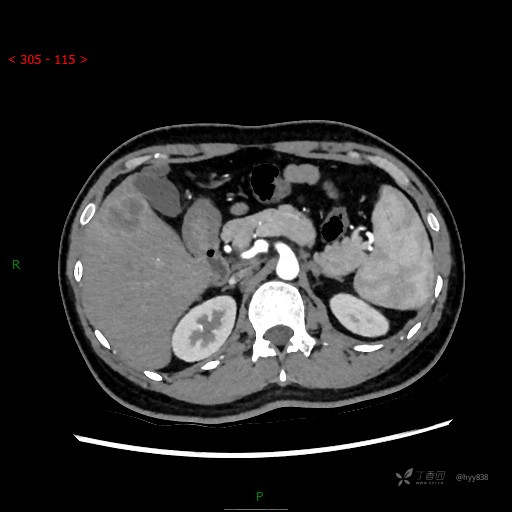

增强动脉期